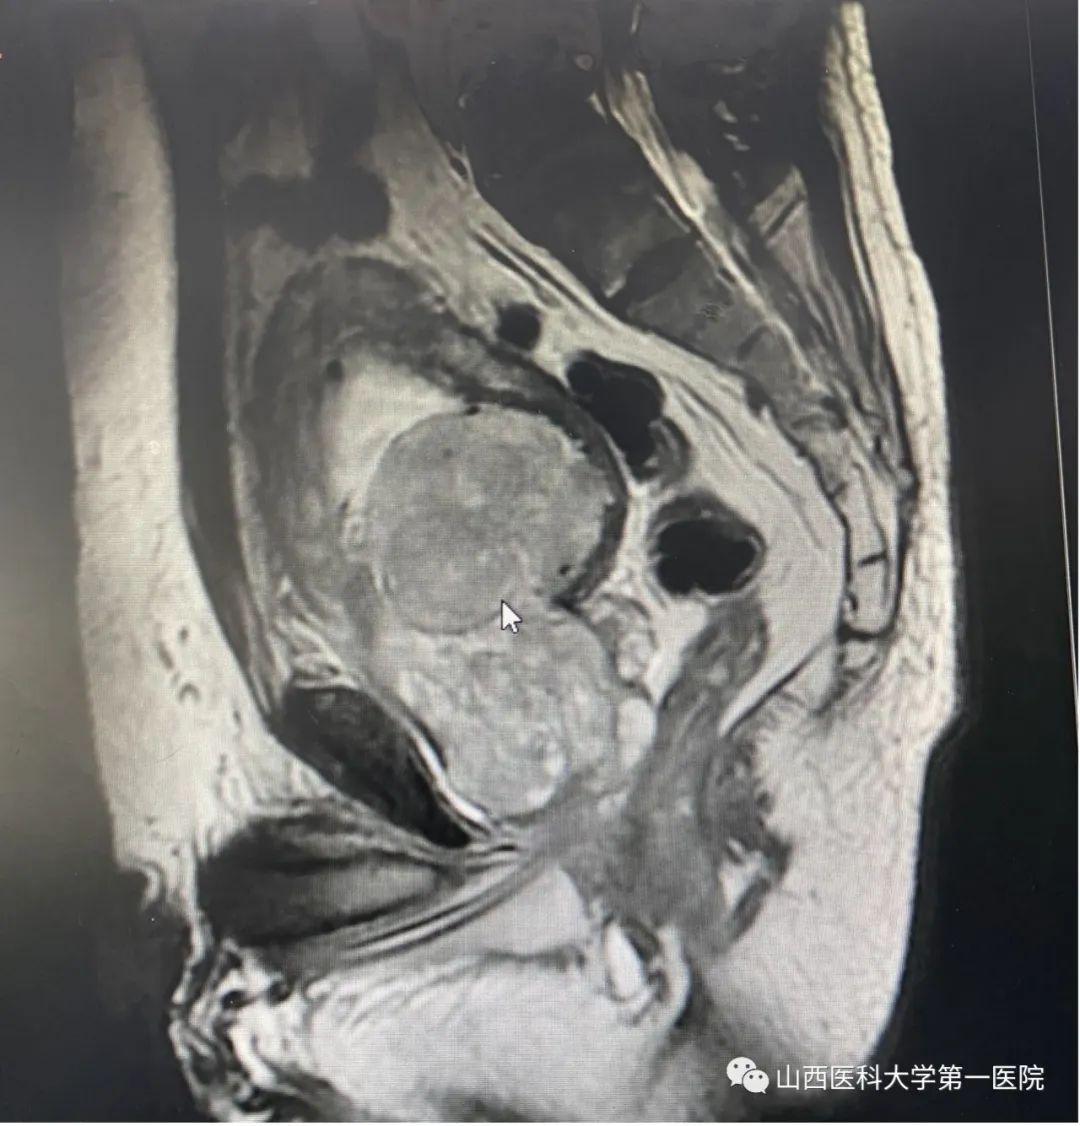

该患者为70岁老年男性患者,以尿频、漏尿为主要症状,长期排尿困难,夜不能寐,10年前曾出现过无法自主排尿,留置尿管病史。尹楠副主任医师详细询问病史及查体后,考虑患者为充盈性尿失禁,收治入院并完善泌尿系彩超检查后结果显示:前列腺左右径7.5cm,前后径12.6cm,上下径11.8cm,残余尿769ml,双肾积水,前列腺估重580g(正常人约为8-20g)。

由于患者前列腺极其巨大,全国少见,泌尿外科前列腺增生亚专业团队详细分析了前列腺形态,评估了膀胱功能并与患者及其家属沟通手术方案后,终决定了实施经尿道铥激光解剖性前列腺剜除术。